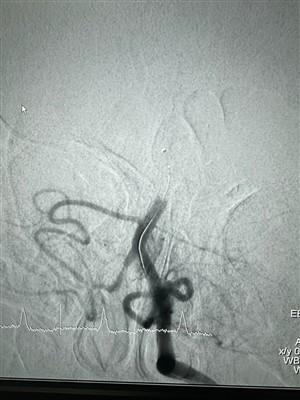

ドレッジャーステント回収機の新たな事例最近、ニューロセーフメディカル社のドレッジャーステントリトリーバーを使用した血栓除去術が成功したケースがありました。ドレッジャーステントリトリーバーは、非侵襲性の柔らかい先端部を備えており、内膜損傷のリスクを大幅に軽減し、血栓を捕捉する独自の特殊形状の穴設計を備えています...

もっと -

新しい症例では浚渫船のステント リトリーバーが使用されています血栓除去期間中(4 時間)の急性右半身不全を患う 48- 歳の男性患者。 Dredger ステント リトリーバー (30x30) を使用した上下枝の途中での血栓除去術の前後。

2024 年 4 月 11 日、SRH Waldklinikum Gera でのエキサイティングな事件!最近、SRH Waldklinikum Gera で医学博士が率いる興味深い症例が実施されました。 クロースナー。 この症例では、Glutton 吸引カテーテル (6F) と Dredger ステント レトリバー (4X40) の併用が行われました。 この手術では、中大脳動脈の頭蓋内血栓除去術に焦点を当てました。

もっと